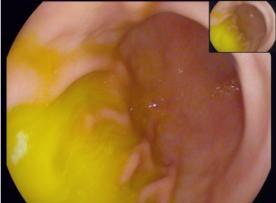

胃食管反流是指胃内容物(如胃液)反流入胃食管腔,引起胃食管黏膜损害并有明显黏膜糜烂、溃疡的一类消化道疾病。因其症状除了反酸、烧心外,还可能伴有咽部不适及胸痛,很容易与其他疾病混淆,所以一定要辩证清楚,以免拖延病情。今天我们就来介绍反流性食管炎的疾病相关内容及如何正确用药。